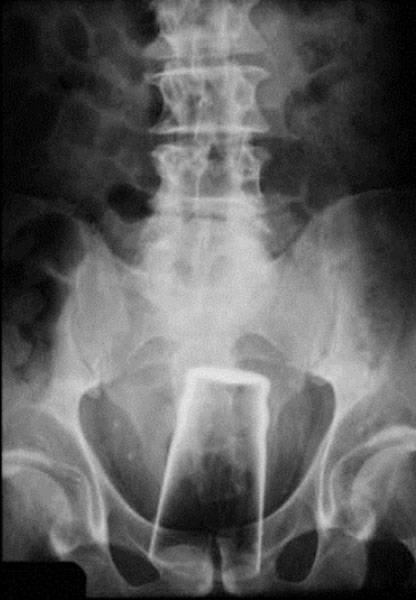

#15 Oluttuoppi